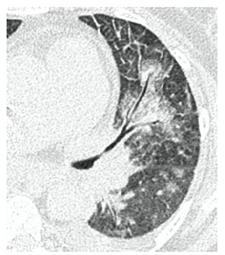

2. Наличие клинических проявлений, указанных в п. 1, в сочетании с характерными изменениями в легких по данным компьютерной томографии (КТ) (см. Приложение 1 настоящих рекомендаций) вне зависимости от результатов однократного лабораторного исследования на наличие РНК SARS-CoV-2 и эпидемиологического анамнеза.

- Изменения при КТ (рентгенографии), типичные для вирусного поражения (объем поражения минимальный или средний; КТ 1-2)

- Изменения в легких при КТ (рентгенографии), типичные для вирусного поражения (объем поражения значительный или субтотальный; КТ 3-4)

- Изменения в легких при КТ (рентгенографии), типичные для вирусного поражения критической степени (объем поражения значительный или субтотальный; КТ 4) или картина ОРДС.

КТ имеет высокую чувствительность в выявлении изменений в легких, характерных для COVID-19. Применение КТ целесообразно для первичной оценки состояния ОГК у пациентов с тяжелыми прогрессирующими формами заболевания, а также для дифференциальной диагностики выявленных изменений и оценки динамики процесса. КТ позволяет выявить характерные изменения в легких у пациентов с COVID-19 еще до появления положительных лабораторных тестов на инфекцию с помощью МАНК. В то же время, КТ выявляет изменения легких у значительного числа пациентов с бессимптомной и легкой формами заболевания, которым не требуется госпитализация. Результаты КТ в этих случаях не влияют на тактику лечения и прогноз заболевания при наличии лабораторного подтверждения COVID-19. Поэтому массовое применение КТ для скрининга асимптомных и легких форм болезни не рекомендуется.